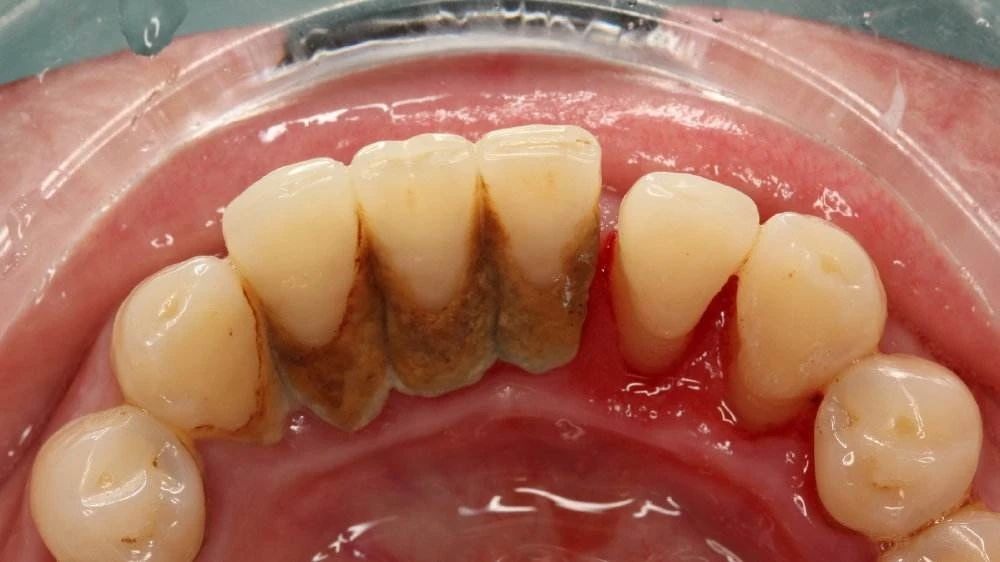

如果你在吮吸、刷牙、咀嚼较硬的食物时出现牙龈出血,那么可以初步考虑为牙龈炎了。牙龈出血正是因为牙龈下有炎症导致的,牙龈发炎的主要因素就是食物残渣残留在牙缝间,平时清洁不到位,时间一长就形成了更难清洁的牙结石,从而给细菌提供了最佳的环境,牙龈组织受细菌感染发生炎症,随后就会有出血的表现。

牙龈出血的根本原因实际上是牙龈发生轻微的萎缩。当口腔中的牙菌斑在牙齿表面形成后,如果不及时清除,便会沉积越厚,最后形成牙结石,而一些较硬的牙结石对牙龈长期产生刺激作用。当正常的牙龈受到炎症的刺激,牙龈的毛细血管增多,开始充血,牙龈颜色随之变暗,一旦受到刺激,就很容易出血。

很多朋友可能还不知道,牙龈炎其实是牙周炎的早期表现,如果长时间不清除牙齿里的牙结石,缓解牙龈的炎症,就容易演变成牙周炎。牙周炎的危害就不用小编多说了吧,搞不好可能连牙齿都保不住,所以症状还不严重的朋友们,疫情后赶紧去正规口腔医疗机构检查处理下。